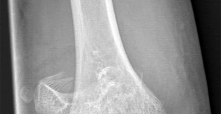

This module contains 50 advanced orthopedic multiple-choice questions meticulously developed to mirror the Arab Board of Orthopedic Surgery examinations. These questions are derived from the clinical teaching case: 1.2.3 Chondroectodermal Dysplasia (Ellis–Van Creveld’s Syndrome).